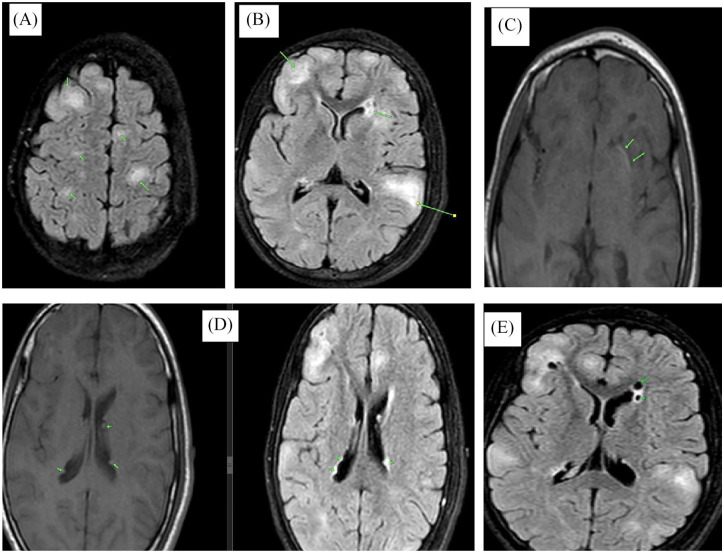

结节性硬化症(TSC)是一种罕见的多系统神经皮肤综合征,具有广泛的临床表现。我们提出一个14岁的青少年女性谁提出了历史的面部血管纤维瘤,因为年龄8个月。查体时发现面部多发血管纤维瘤及其他多发性皮肤表现。头部和腹部MRI显示皮质结节,多发双侧脑室周围和室管膜下结节病变,钙化,双侧肾脏肿大伴多发大小不等的双侧肾脏血管平滑肌脂肪瘤,双侧多囊肾背景,胸部MRI未见明显变化。诊断TSC采用临床诊断标准,其中包括主要和次要特征。由于缺乏资源,无法通过基因研究进行诊断。管理是多学科的,需要每6个月定期监测一次,以监测疾病进展并在出现并发症时进行管理。该病例说明了在资源匮乏的环境中,如赞比亚,需要多学科方法来解决TSC的各种临床表现,以及TSC的诊断挑战、治疗限制和心理影响,因为那里获得先进治疗的机会有限。

Tuberous sclerosis complex (TSC) is a rare multisystemic neurocutaneous syndrome with a wide spectrum of clinical manifestations. We present a case of a 14-year-old adolescent female who presented with a history of facial angiofibromas since the age of 8 months. Physical examination was remarkable for multiple angiofibromas on the face, and other multiple cutaneous manifestations of TSC. MRI of the head, and abdomen revealed cortical tubers, multiple bilateral periventricular and subependymal nodular lesions, calcifications, and bilateral kidney enlargement with multiple bilateral renal angiomyolipomas of varying sizes in a background of bilateral polycystic kidneys, MRI of the chest was unremarkable. A diagnosis of TSC was made using the clinical diagnostic criteria which consist of major and minor features. A diagnosis using genetic studies could not be made due to a lack of resources. Management was multidisciplinary and regular monitoring every 6 months will be required to monitor disease progression and manage complications as they arise. This case illustrates the multidisciplinary approach needed to address the diverse clinical manifestations of TSC and the diagnostic challenges, treatment limitations, and psychological impact of TSC in low-resource settings like Zambia where access to advanced therapies is limited.